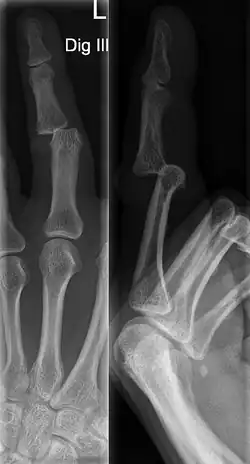

A jammed finger can generally be diagnosed by a physical examination. Bone or joint deformity may indicate potential dislocations or fractures.[6] The basic structure of the finger includes three bones with joints in between each.[9] The joint closest to the tip is the distal interphalangeal (DIP) joint. The next joint, moving closer to the hand, is the proximal interphalangeal (PIP) joint. The thumb differs by only having two bones and one interphalangeal joint.[10]

The injured finger may be examined to determine where the pain is worst.[3] If the finger is sprained or dislocated, pain will be worse at the joint rather than the bone.[3] Due to the risk of dislocations or fractures, X-rays should be conducted prior to testing joint stability. This allows for prior detection of a dislocation or fracture.[3] It is recommended that a variety of views (lateral, oblique, and anteroposterior) are observed.[3] In extremely painful cases, a digital nerve block may be done to better assess the finger. This is where anesthetic is injected to either side of the base of the affected finger to reduce pain.[3]

DIP dislocations are much less common than PIP dislocations.[3] This is thought to be due to the increased stability of the DIP joint,[15] though not for certain.[2] Dislocations can be categorized based on the direction that the fingertip moves in relation to the knuckle.[6] If in the direction of the palm, it is a volar dislocation. If in the direction of the back of the hand, it is a dorsal dislocation.[6] If in the direction to either side, it is a lateral dislocation.[2] Of the three, dorsal dislocations are most common.[6] Dorsal dislocations of the PIP commonly lead to volar plate damage.[2]

Dislocations are often visually obvious due to joint deformity.[2] Therefore, x-rays may or may not be utilized in the diagnosis of a suspected dislocation. Though, they can provide feedback on post-reduction status if attempted prior to formal medical evaluation.[2] Dislocations may also be complicated by a tandem fracture.[5] These cases may necessitate a visit to a hand surgeon for surgery.[2]

Fractures

Fractures are instances where the bone's structural integrity has been compromised.[20] If a jammed finger produces a fracture, pain will be greatest at the bone as opposed to the joint.[2] There may also be visual deformation of the bone itself.[6] As with any skeletal injury, an x-ray can be conducted to verify the presence of a fracture.[1] The distal phalanx is especially vulnerable to avulsion fractures.[1] These avulsion fractures are common following a first time dislocation of the DIP.[1]